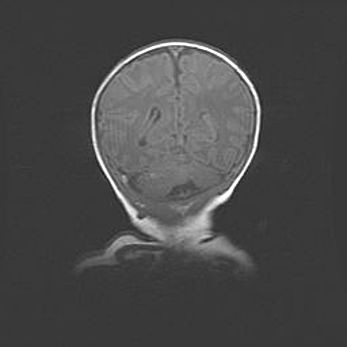

Сообщающаяся гидроцефалия. Кистозная энцефаломаляция головного мозга.

Возраст: 3 месяца 4 дня

Вес: 3100 г

Пол: женский

Окружность головы: 34 см

Срок гестации: 31 неделя

Кистозная энцефаломаляция головного мозга - одна из форм поражения головного мозга в детском возрасте. Характеризуется возникновением множественных и распространённых кист в коре, белом веществе и подкорковых образованиях головного мозга у плодов, новорождённых и детей раннего возраста. Развитие кистозной энцефаломаляции связано с внутриутробной асфиксией и гипотонией, родовой травмой, тромбозом синусов, пороками развития сосудов, инфекциями, сепсисом и другими причинами. Наиболее значимые инфекционные агенты: вирусы простого герпеса, цитомегалии, краснухи, токсоплазмы, энтеробактерии, золотистый стафилококк и другие.